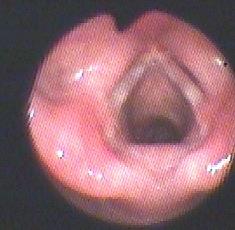

1.2诊断标准与方法对于可疑SGH患儿均需行纤维喉镜检查,声门下单侧或双侧局部隆起,表面光滑、暗红色,阻塞声门下气道,则高度怀疑SGH(图1)。颈部增强CT见声门下局部软组织增厚,气道变窄,增强扫描强化明显(图2a,b,c),诊断明确后给药。

1.3用药方案用药前需完善血糖、血压、生化、心电图、心脏超声等检查,排除禁忌后收住院,心电监测下给药,普萘洛尔起始剂量为1mg/kg·d,分3次口服。如无异常,第2天加量至1.5mg/kg·d,并维持该剂量出院继续居家服药,门诊定期随访内镜、血糖、血压、心电图等,剂量不再增加,直至治疗结束。当患儿无喉喘鸣等临床症状,内镜检查或者颈部增强CT显示声门下血管瘤消失,可以停药。(见图1b)。

a.治疗前见声门下左侧壁红色、光滑隆起。

b:口服普萘洛尔治疗1年后复查喉镜,声门下血管瘤消失。